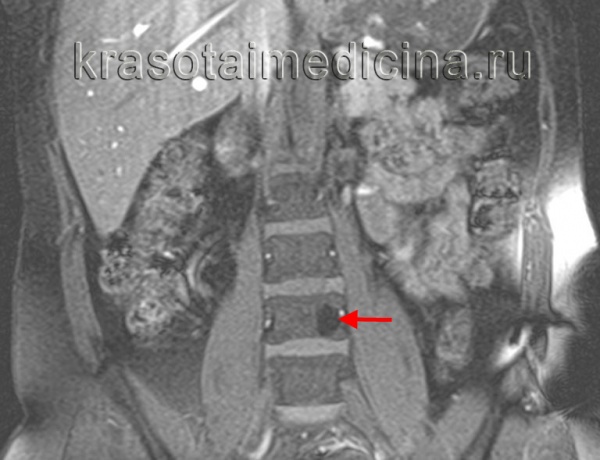

(Слева) На аксиальной МРТ (Т1 ВИ) определяются признаки агрессивной гемангиомы грудного позвонка с распространением в задние отделы и эпидуральное пространство. Жир визуализируется лишь в одной области. Точечный рисунок обусловлен трабекулами в гемангиоме.

(Справа) На сагиттальной МРТ (Т2 ВИ) визуализируется агрессивная гемангиома с гиперинтенсивным сигналом и легко различимым крупным эпидуральным компонентом. Видны также другие гемангиомы.